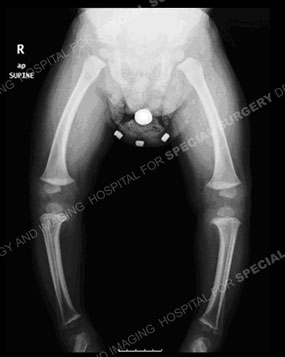

This is a good looking xray, the legs are equal length with straight weight bearing line from the hip through the center of the knee to the ankle. But this teenager started with both legs bowed way out here with a leg length difference. He walked with pain and struggled to get through each day. Thankfully, #refuahhelpline connected him with me. I counseled him that I could help him, one leg at a time, by reshaping his bone as shown here. On the left side I would remove a wedge of bone from above his knee and stabilize him with a plate. One his right side, I described more was needed. I would remove the bone from the femur to straighten it, and insert it into the tibia make it straight as well and also hasten his healing. I performed his two surgeries, and now his legs are straight, leg lengths equal, he is walking great, long distances without pain, and it’s time to remove the plates!